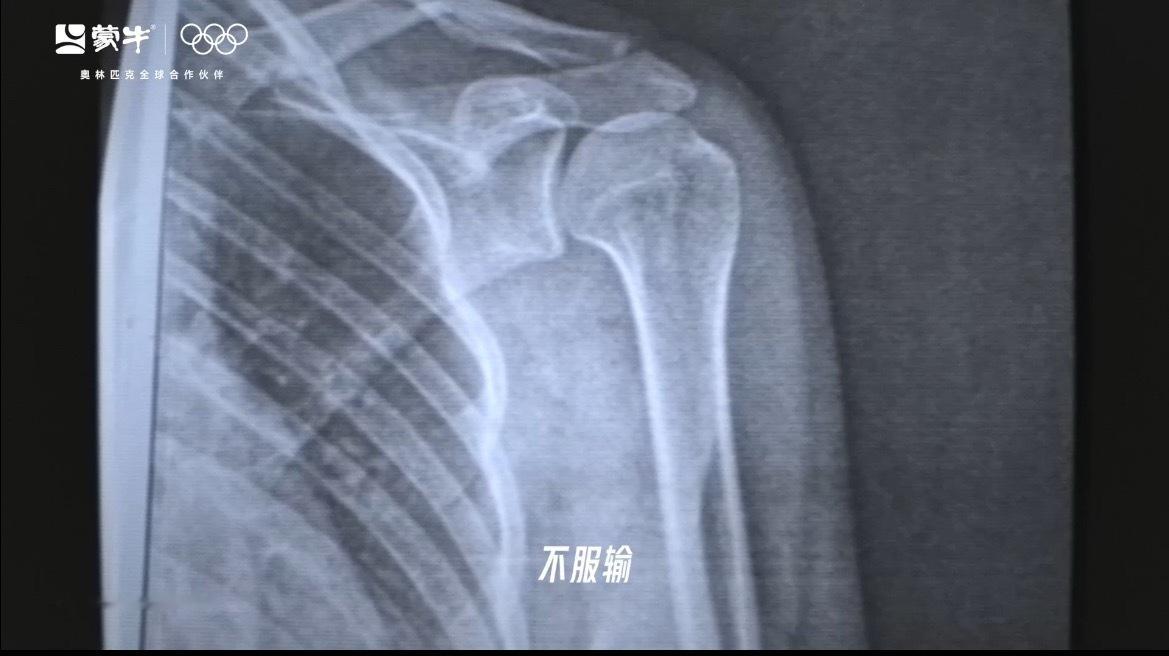

雪道上的每一个弯道,都是与自己的较量。看她一次次摔倒,又一次次重新站起,冰晶沾满护目镜,却遮不住眼底的光。这不仅是运动员的日常,更是每个时代奋斗者的真实写照——在各自的赛道上,面对挫折不改其志,历经风雨不褪其色。